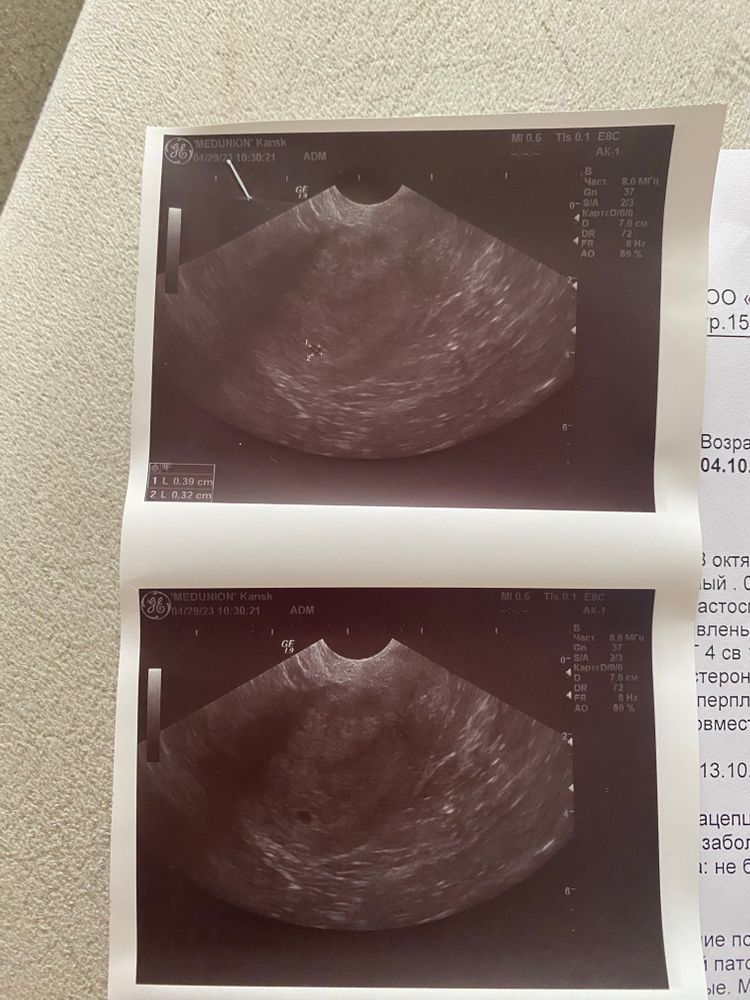

Мария в Зачатие 3 года Девочки,подскажите с узи Девочки,дата зачатия 8 апреля. Сейчас срок по узи 3-4 недели. Я не могу понять где размеры точечки смотреть. Видела у кого-то,что врач прям прописывает размеры,у меня ничего нет. Первая беременность,я вообще в этом не соображаю😇 Посмотрите еще 20 записей на эту тему Отменить Ответить Екатерина На первом снимке точечка с цифрами 1 и 2. Внизу слева на этом же снимке есть таблица. Это ее замеры. 29.04.2023 Ответить Best mammy У вас на снимке два размера ПЯ 0,39 см и 0,32 см 29.04.2023 Ответить Мария Дарья, а это не сильно маленькие размеры для 3 недель? 29.04.2023 Ответить Имя Мария , скажите спасибо что вообще увидели. Рано еще 29.04.2023 Ответить Best mammy Мария , отличные размеры для вашего срока, вы беременны! 💖 29.04.2023 Ответить Zyzy Маленькие вы еще) подрастите чуть-чуть и снова на узи 29.04.2023 Ответить Имя Заключение покажите 29.04.2023 Ответить Мария Грозовой фронт, 29.04.2023 Ответить Имя Мария , это осмотр и рекомендации гинеколога. Где заключение по узи? 29.04.2023 Ответить Мария Грозовой фронт, это все,что мне отдали 29.04.2023 Ответить Имя Мария , ну вот нет заключения узи. Но по снимку тут пя 3-4мм. Не больше. 29.04.2023 Ответить Сашка На снимке не пишут, пишут в заключении 29.04.2023 Ответить Рузанна Пхачияш В заключение должно быть написано либо плодное яйцо либо ПЯ 29.04.2023 Ответить Прогестерон Какая-то ерунда творится Чаты Беременных Выберите чат: Январята-2026 Февралята-2026 Мартята-2026 Апрелята-2026 Майчата-2026 Июнята-2026 Июлята-2026 Августята-2026